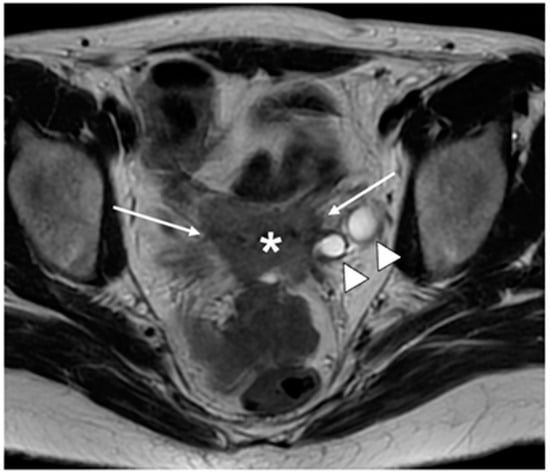

| IIB | With parametrial invasion but not up to the pelvic wall |